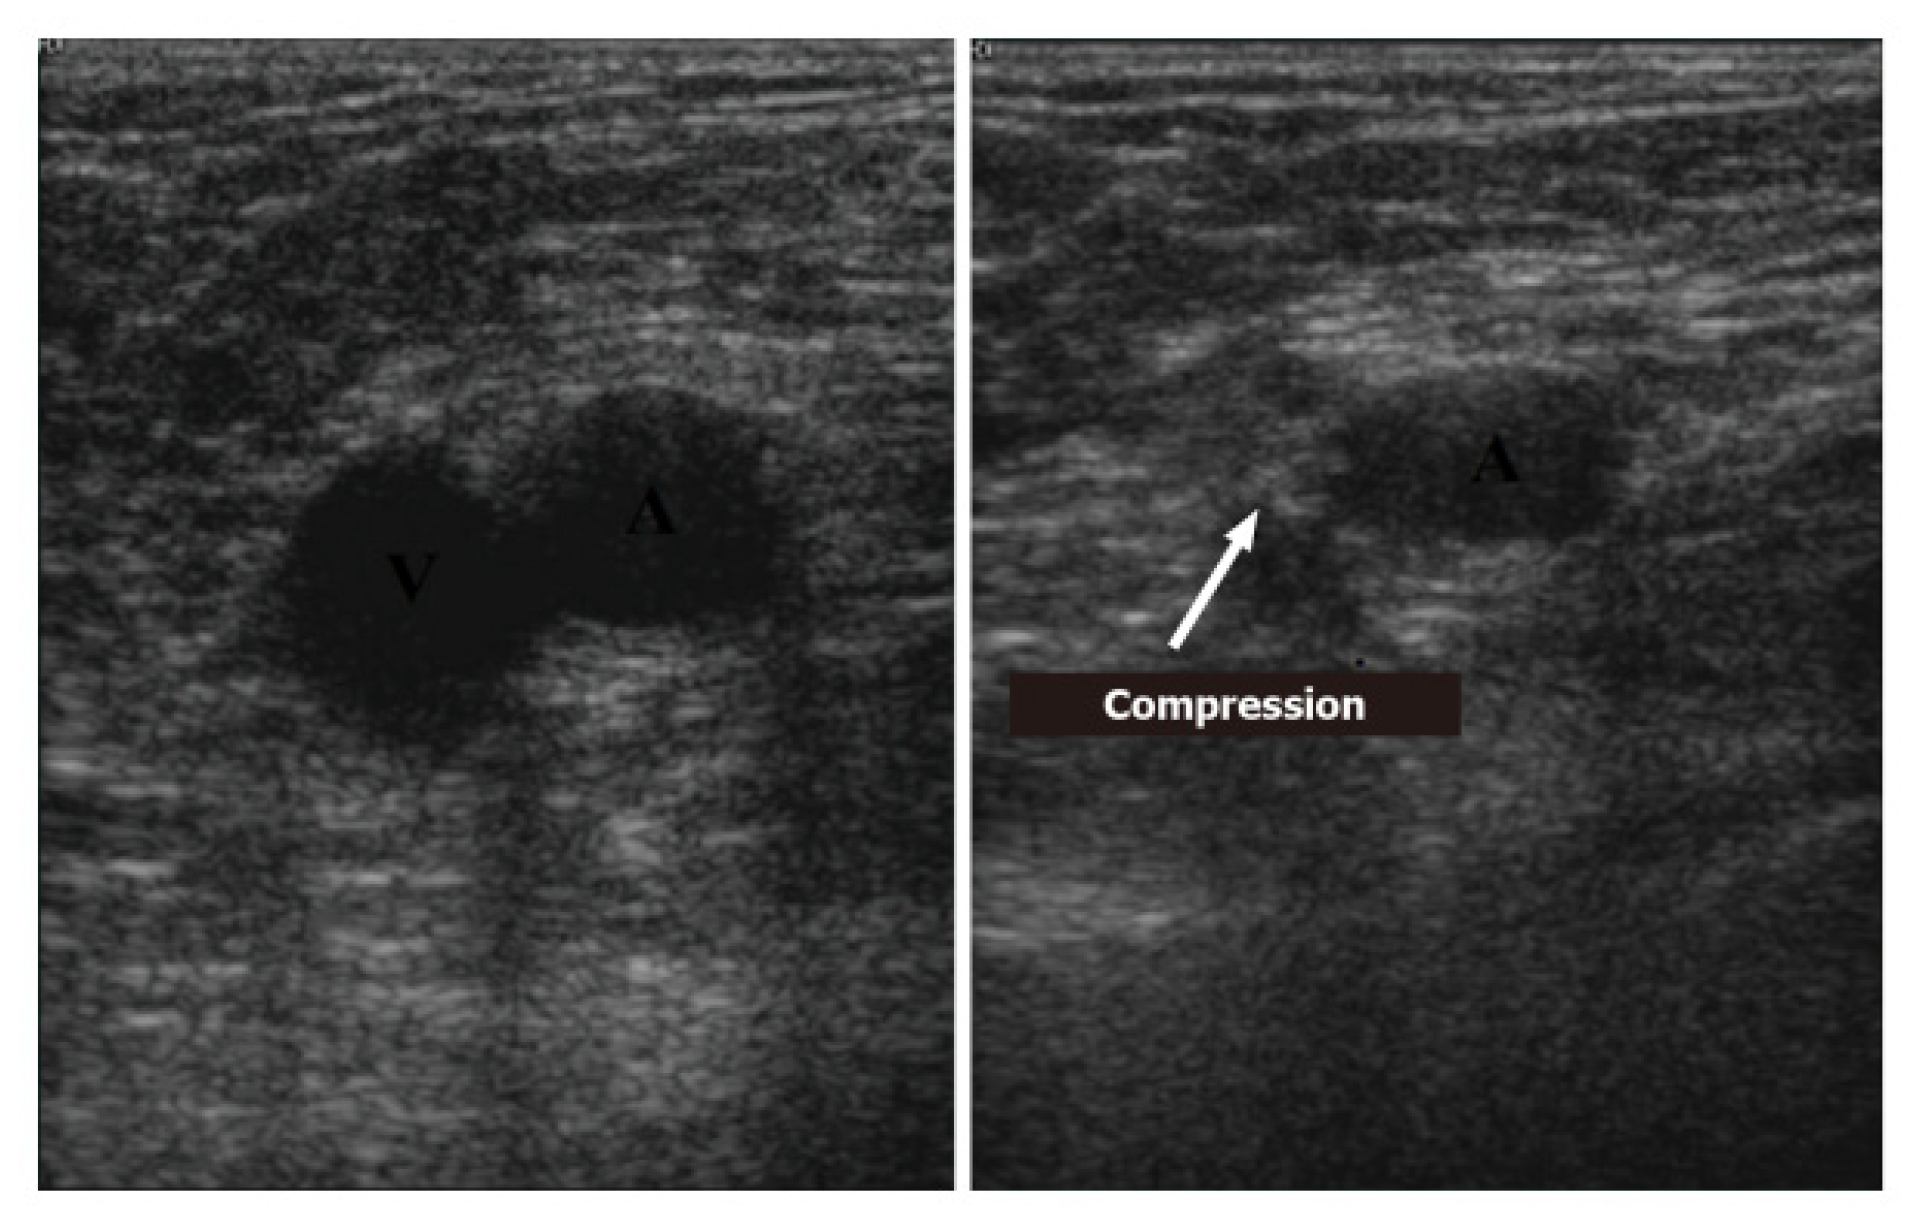

5. Deep-Vein Thrombosis

5.1. Protocol

5.2. Imaging

- Acute: the thrombus itself may not be visible. If detected, it is deformable with the force applied on the probe and with a regular surface; it is a distended vein.

- Subacute thrombus: (before six months and after clot formation) intermediate morphological changes that cannot be included in the chronic phase.

- Chronic post-thrombotic change: not compressible nor deformable with an irregular surface; the vein caliber may be normal or reduced.